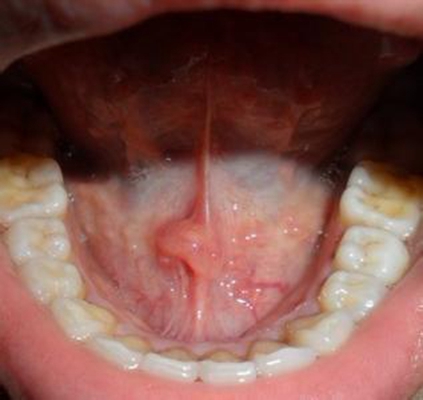

口腔癌圖片

口腔癌的前兆 (6)

口腔癌的前兆 (7)

口腔癌的前兆 (8)

口腔癌的前兆 (9)